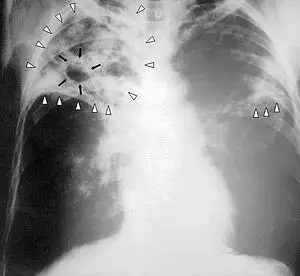

Tuberculosis-x-ray-1.jpg

Chest X-ray of a person with advanced tuberculosis: Infection in both lungs is marked by white arrow-heads, and the formation of a cavity is marked by black arrows.